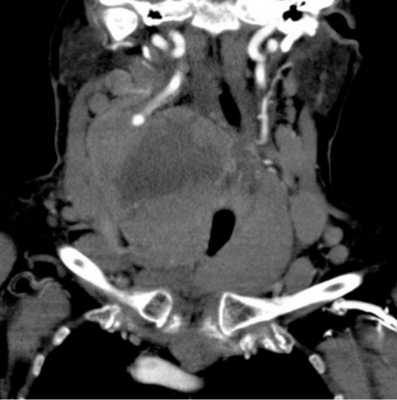

Опухоль паращитовидной железы на снимке компьютерной томограмме

Исследование с контрастом позволяет точно определить местоположение и размеры паращитовидных желез, даже если они находятся в загрудинном пространстве.